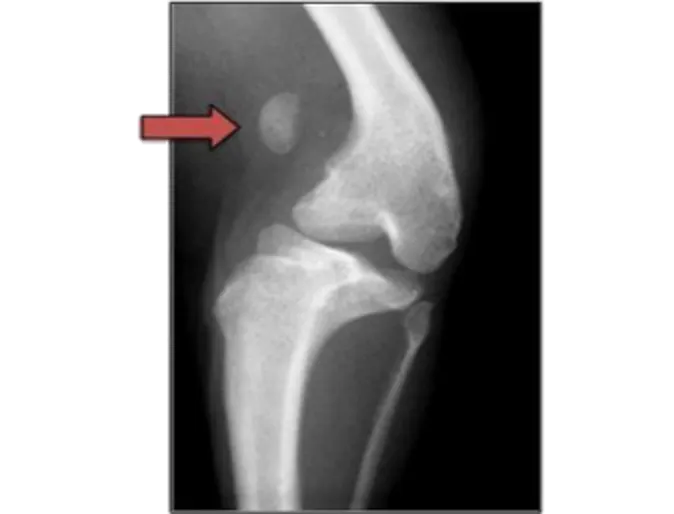

The radiographs above show a normal canine stifle and a stifle with a Grade IV patella luxation. On the normal radiographs the patella, indicated by the blue arrow, is difficult to see as it lies on top of the femur. In the Grade IV MPL the patella, pointed out by the red arrow, is “floating” in space instead of being properly positioned over the femur. In addition, the femur and tibia are abnormally curved. All of this results in hind limb deformity and persistent lameness or an abnormal gait. (Courtesy Dr. Sharon Kerwin of Texas A&M University)